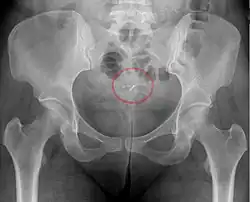

- A "lost coil" occurs when the thread cannot be felt by a woman on routine checking and is not seen on speculum examination.[64] Various thread collector devices or simple forceps may then be used to try to grasp the device through the cervix.[65] In the rare cases when this is unsuccessful, an ultrasound scan may be arranged to check the position of the coil and exclude its perforation through into the abdominal cavity or its unrecognised previous expulsion.